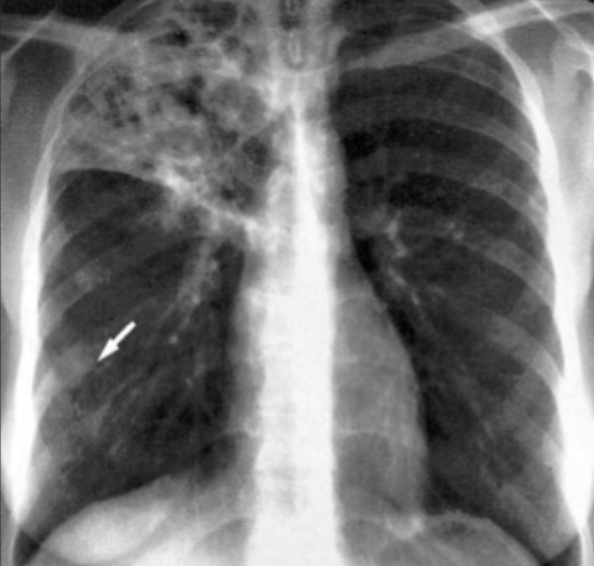

Q

What is this ?

A

Reactivated TB

-cavitation in upper lobe

-cavities caused by immune response (poor immune system dont get this really)